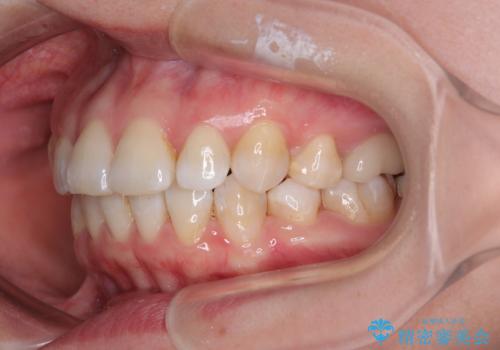

- 上下前歯の後戻りを気にして来院された患者様です。

インビザラインでの治療を希望されていて、デコボコの程度が中等度であり、安価なパッケージにて対応可能と判断されたため、インビザライン・モデレートを用いて矯正治療を行うこととしました。

インビザライン・モデレートは、製作できるアライナーの枚数に制限があるため、移動可能な量に限りがあるものの、インビザライン・ライトよりも枚数が多いため、幅広い症例に対応可能です。